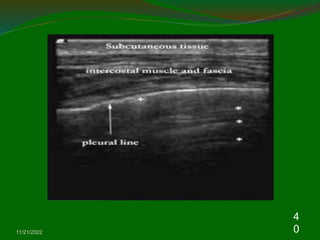

3. Chest wall: Muscle layers, bone, and

pleura

Because air cannot be visualized by US, the

normal lung parenchyma cannot be detected by

US theoretically.

The image of chest US in chest wall including

muscle, fascia, bone, and pleura .

The soft tissue echogenicity with multiple layers

means muscles and fascia.

The normal ribs appear hyperechoic surfaces

with prominent acoustic shadows beneath the

ribs.

Approximal 0.5 cm below the ribs shadows,

the visceral and parietal pleura appear as an

enchogenic bright line.

During respiratory movement, the two pleural

lines glide with each other which is referred to

as the “Gliding sign”. Therefore, the “Gliding

sign” means normal parietal and visceral

pleura slide over each other during respiration

and the loss of “Gliding sign” can be seen in

pneumothorax or diffuse pleural thickening